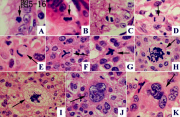

| 2021年12月10日 (五) 13:14 | 12号切片-异物肉芽肿(虫卵及异物巨细胞)-镜下观3.jpg (文件) |  |

109 KB | Cirno.9 | 基于MsUpload的文件上传 | 1 |

| 2021年12月10日 (五) 13:14 | 12号切片-异物肉芽肿(虫卵及异物巨细胞)-镜下观2.jpg (文件) |  |

117 KB | Cirno.9 | 基于MsUpload的文件上传 | 1 |

| 2021年12月10日 (五) 13:14 | 12号切片-异物肉芽肿(虫卵及异物巨细胞)-镜下观1.jpg (文件) |  |

161 KB | Cirno.9 | 基于MsUpload的文件上传 | 1 |